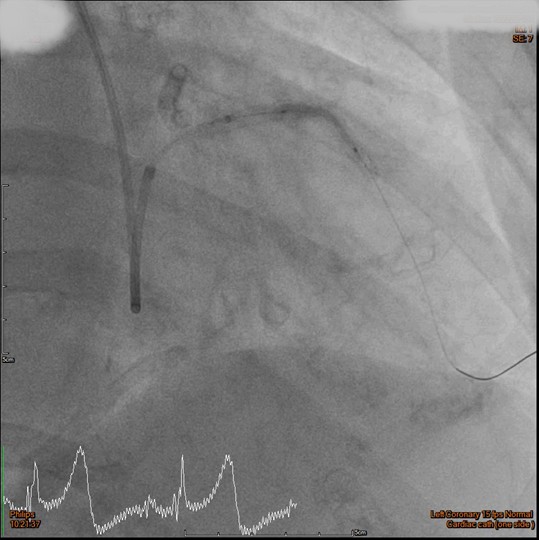

The RCA was calcified but no significantly severe stenosis.The LCX was calcified with mild stenotic lesion and a patent old stent.The LAD was severely calcified with an under-expanded old stent at middle to distal part. The lesion was also severely stenotic. The proximal to middle LAD had moderately stenotic lesion with calcification also.

Initially, we tried to insert IVUS catheter but unable to cross the lesion. We tried a NC balloon but unable to cross it also.Hence, we used rotational atherectomy with 1.5mm burr. However, the burr was unable to cross lesion even in high speed and entrapped in the stent.We removed the burr in guide extension catheter then the NC balloon could cross the lesion. The IVUS cather could also cross it with guide extension catheter support. The stent was almost not expanded. We tried NC balloon high pressure dilation but balloon slippage and burst. The lesion was still un-dilatable. We insert cutting balloon which avoided slippage but remained burst. We escalated the burr size to 1.75mm. The larger burr was not stucked but still unable to cross lesion. Besides, the larger burr causing slow blood flow. After adenosine injection, the patient's blood flow recovered. We reduced the burred size to 1.25mm which cross the lesion once but entrapped while doing polishment. After burr retrieval, we used NC balloon high pressure dilation. The balloon bursted but the lesion remained un-dilatable.Finally, the lithotrypsy balloon could cross the lesion and eliminate 80 pulses. The lesion was expanded much well. The IVUS showed the old stent was expanded and calcium was cracked. We deployed a new stent for old one destruction and proximal dissection. The final IVUS image showed epansion and apposition were accpetable.